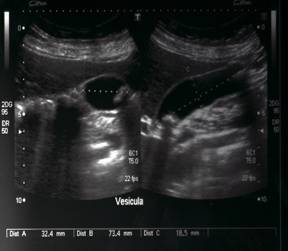

Al día siguiente de hospitalización se solicita exámenes de imagen tales como ecografía abdominal donde se observa hígado normal, con vesícula distendida, con paredes lisas, con pólipo en su interior y colédoco libre. Ecografía del cuello reporta una glándula tiroidea con presencia de un nódulo con micro–calcificaciones en lóbulo derecho (Figuras 1-4).

Una vez revisados los nuevos paraclínicos, la paciente es mantenida con la misma dosificación de Levotiroxina de 50mcg vía oral al día en ayunas. A los tres meses de tratamiento se observa una mejor condición de la paciente la sintomatología depresiva ha mejorado continua tomando la Levotiroxina a dosis de 50mcg diarios y la Fluoxetina 50 mg diarios, una dieta adecuada y terapia física. Se realizan nuevos controles de sangre con resultados normales (Tabla 4) y una nueva ecografía tiroidea en la cual se observa mejor las características ecográficas del nódulo tiroideo previamente observado, describiéndose semisólido, encapsulado de 3,7cm, clasificación de riesgo TIRADS 4 (Figuras 5–6). Se le explica a la paciente el riesgo que ofrece un nódulo de éste tipo, pero ella rehúsa realizarse la Punción por Aguja Fina guiada por ultrasonido para la valoración citológica del nódulo tiroideo.